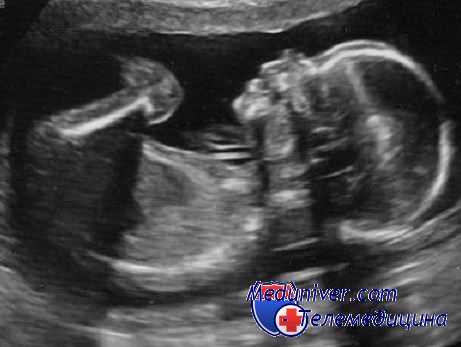

Во всех немногочисленных случаях, выявленных пренатально, плоды-«паразиты» имели вид смешанной опухоли. Типичная картина характеризуется наличием четко отграничивающей капсулы у образования, внутри которого выявляется гиперэхогенная масса, погруженная в жидкость или частично окруженная жидкостью. Иногда диагноз можно заподозрить при обнаружении структур рудиментарного позвоночника.

Плод в плоде (плод-«паразит») представляет собой инкапсулированную солидную опухоль, которая имеет питающую ножку. Он является аномальным «паразитирующим» плодом, внедренным внутрь другого плода («хозяина», или, иначе, аутозита) при монозиготной монохориально-диамниотической двойне. В наиболее типичных случаях плод-«паразит» имеет вид образования, окруженного фиброзной мембраной (эквивалент хориальной и амниотической оболочек), внутри которого содержатся жидкость (эквивалент околоплодных вод) и плод, подвешенный на пуповине или сосудисто-тканевой ножке.

Интраоперационно при наличии «плода в плоде» обнаруживается четко отграниченное образование, покрытое фиброзной мембраной. Внутри этого образования собственно плод-«паразит» подвешен на сосудистой ножке и погружен в жидкость соломенного цвета. Сосудистая ножка представлена двумя сосудами (артерией и веной). Жидкость, количество которой, как правило, невелико, содержит жир. Происхождение этой жидкости неизвестно.